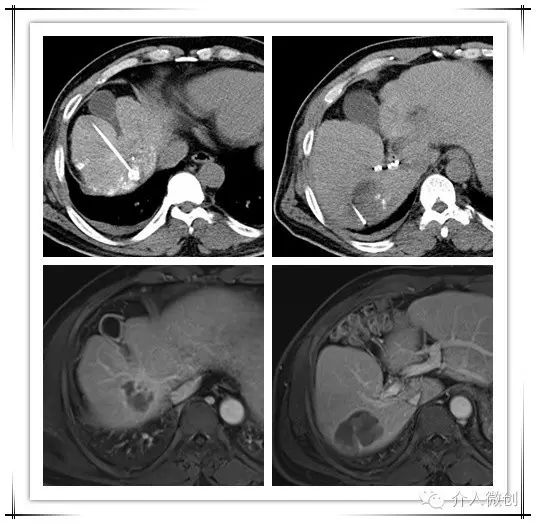

CT引导下肝癌射频消融术+门脉癌栓放射性粒子植入术,术后2周复查肝脏MRI提示肝内病灶得到有效控制,甲胎蛋白(AFP:14 ug/ml)亦明显下降,术后1个月甲胎蛋白已降至正常范围(AFP:3.9 ug/ml)

射频消融+放射性粒子植入